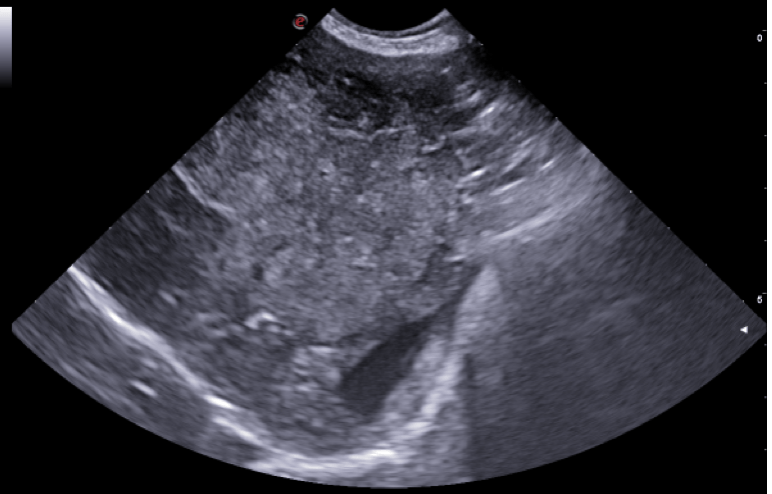

Tra i servizi che l’Ospedale Veterinario Città di Conegliano fornisce, non mancano quelli di diagnostica per immagini:

ecografia, radiologia digitale, TC.

Gli specialisti Roberto De Pellegrin e Riccardo Pelizzon, in particolare, si occupano degli esami ecografici, ecocardiografici, tomografici per l'acquisizione di immagini del corpo del paziente attraverso l'esposizione a ultrasuoni o a raggi X.

Si tratta di esami non invasivi né dolorosi, che possono essere eseguiti molto rapidamente.